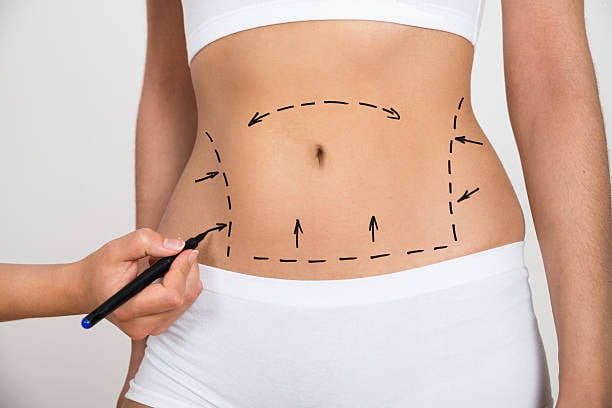

تعد عملية شفط الدهون في الرياض واحدة من الخيارات الرائجة لتحسين مظهر الجسم واستعادة الثقة بالنفس. تُقدم هذه العملية حلولًا فعالة للأشخاص الذين يسعون للتخلص من الدهون الزائدة في مناطق محددة من الجسم والتي قد لا تستجيب للحمية الغذائية أو التمارين الريا...

شفط الدهون هو إجراء جراحي تجميلي يستخدم للتخلص من الدهون الزائدة في مناطق معينة من الجسم التي يصعب التخلص منها عن طريق الرياضة أو النظام الغذائي. في الرياض، أصبح شفط الدهون خيارًا شائعًا للعديد من الأشخاص الذين يسعون لتحسين مظهرهم واستعادة ثقتهم بأنف...

عملية شفط الدهون في الرياض هي واحدة من أبرز الإجراءات التجميلية التي يسعى الكثيرون إلى إجرائها لتحقيق جسم أكثر تناسقًا ووزنًا مثاليًا. تُعد هذه العملية خيارًا مثاليًا للأشخاص الذين يعانون من تراكم الدهون في مناطق معينة من الجسم ولا يمكنهم التخلص منها...

شد البطن في الرياض هو الحل المثالي لأولئك الذين يسعون للحصول على بطن مشدود ومسطح. مع تقدم العمر أو بعد الحمل أو فقدان الوزن، قد يظهر التراكم الدهني أو الترهل في منطقة البطن، مما يسبب الإزعاج للكثيرين. في هذه المقالة، سنقدم لكِ كل ما تحتاجين معرفته عن...